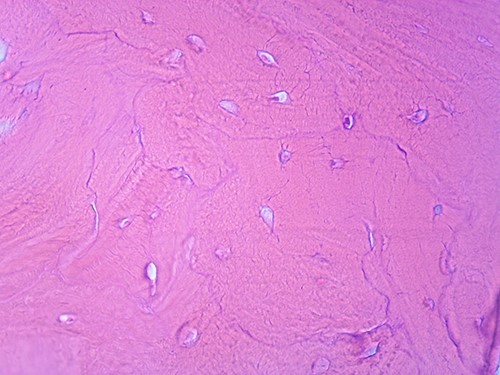

We present a case of a 49-year-old, female patient who presented at our clinic complaining of a growing painful mass with a diameter of ⁓3 cm in her left calf. The patient noticed the mass 2 months before the clinical exam and according to the anamnestic data it was growing progressively, becoming more painful, but only when touched, not spontaneously. She was first seen in another clinic, an ultrasound was performed and excision in local anesthesia was suggested. On presentation, clinical and ultrasound examinations were performed. Clinical exam revealed presence of a soft tissue mass on the medial side between the proximal and medial third of the left calf, of ⁓3 cm. It was placed deep in the subdermal area, mobile and not connected to the fascia. The ultrasound showed a heterogeneous, but predominantly hypoechoic mass with increased through transmission and increased vascularization (Fig. 1). Magnetic resonance imaging (MRI) was performed, confirming the presence of a soft tissue tumor in the subcutaneous tissue of the left calf (Fig. 2). Wide resection of the mass under spinal anesthesia was scheduled. Macroscopy of the specimen showed a whiteish soft fragment measuring 2 × 2 × 0.8 cm, microscopically composed of fibroblastic stroma with myxoid degeneration and immature osteoid embedded in between atypical osteoblasts with inconspicuous mitotic activity (Fig. 3). Foci of chondroid matrix with atypical chondrocytes were present. Necrotic and calcified bony trabeculae with osteoblastic rimming and adipose tissue with skeletal muscle were present on the periphery. The proliferative index, Ki67 was ⁓5%, thereupon a diagnosis of low-grade ESOS was made (Fig. 4). The regular staging follow-up was performed with chest and abdominal computed tomography (CT). No signs of metastatic disease were detected. The bone scan with Tc99m showed an increased uptake on the left iliac bone, highly suspected of Paget disease. Another surgery was scheduled. This time, re-resection procedure to achieve negative margins, as well as a biopsy of the iliac wing was performed. Negative margins were accomplished with the re-resection procedure. Grossly, the iliac bone biopsy was composed of five bony fragments measuring 0.5–1.5 cm. Microscopy showed sclerotic and irregularly shaped anastomosing, lamellar bony trabeculae with focal irregular calcification. The trabeculae contain osteocytes without atypia, rimmed with reactive osteoblasts, as well as multinucleated osteoclast giant cells. Granulation tissue with focal collagen deposition was present focally in between the bone trabeculae. Focal bone marrow was present. The microscopic analysis was consistent with the late (sclerotic) phase of Paget disease of bone (Fig. 5). On the last follow-up exam, 2 years after the surgery there is no evidence of local recurrence.

Microscopic appearance, from the biopsy of the iliac wing, showing late (sclerotic) phase of Paget disease, He-Eo, ×200.